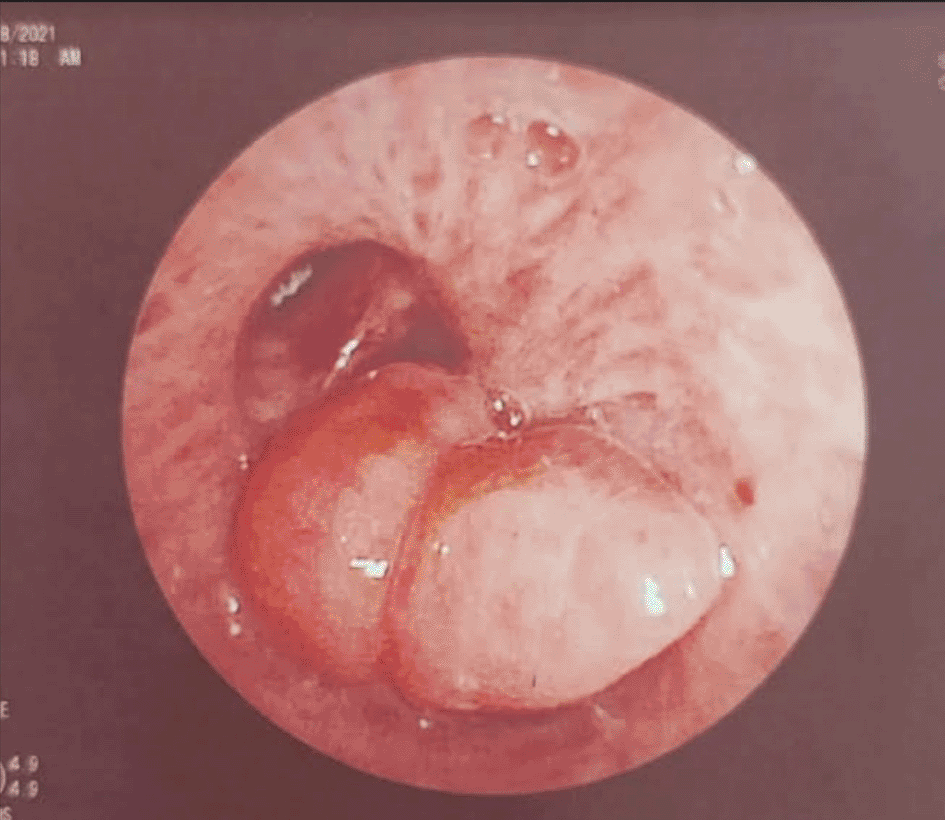

A 58-year-old male with a continued 70-pack-year smoking history was referred to our department for the endoscopic treatment of an endotracheal tumor. Four years previously, the patient presented with isolated shortness of breath and was treated for chronic obstructive pulmonary disease (COPD). Physical examination showed wheezes, and spirometry had met the GOLD criteria for the diagnosis of COPD with very severe airflow limitation (post-bronchodilator FEV1: 1.02 L (29%), post-bronchodilator FEV1/FVC ratio: 45%). The patient was subsequently hospitalized for bilateral hypoxemic pneumonitis and acute respiratory failure, which was treated as COPD exacerbation with a good evolution under usual treatment. On admission in our department, his clinical examination was normal, and his oxygen saturation was 97% (room air). Laboratory tests and chest radiography revealed no abnormalities (Figure 1). Chest computed tomography (CT) scan showed a hypodense pedunculated budding lesion of the left anterolateral tracheal wall located just above the carina, 12 cm from the vocal cords and measuring 17 × 15 × 10 mm (Figure 2). Flexible bronchoscopy confirmed an endotracheal lesion, but biopsies were non-contributory. Based on these findings, laser-assisted mechanical resection of the tumor has been validated as a feasible treatment option. Rigid bronchoscopy, performed under general anesthesia, revealed a non-vascularized pale pink tumor located at the lower third of the trachea approximately 1 cm distal to the carina, which obstructed 60% of the tracheal lumen (Figure 3A). Following the initial exploration, the tumor was removed at the tip of the bronchoscope following laser treatment (15W,364 J). No other instrument was used. On the final examination, a small tumor residue was observed (Figure 3B). There were no complications, and the patient was rapidly discharged. The tumor measured 18 × 10 mm (Figure 4). Histopathological examination of the samples stained with Hematoxylin and Eosin (H&E) showed the presence of hypertrophic seromucous gland admixed with variable amounts of fibrous adipose tissue, spindle cells, and myxoid stroma (Figure 5). The diagnosis of endobronchial HC was established. The patient subsequently underwent follow-up flexible bronchoscopies, which all revealed that the tumor residue was stable and did not obstruct the tracheal lumen with a follow-up of three years (Figure 6). The patient is currently asymptomatic, and his last spirometry examination revealed no abnormalities.

(A): A pale pink tumor at the lower third of the trachea. (B): A small tumor residue.